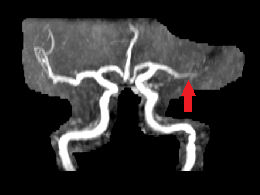

L'acquisition des images a été réalisée lors du séjour du patient en ré-éducation, 6 mois après l'apparition des symptômes. Les séquences permettent de mettre en évidence un AIC carotidien droit au stade chronique (hyposignal en pondération T1 et hypersignal en pondération T2) avec atrophie du tissu cérébral de l'hémisphère droit. L'angiographie-IRM (ARM) des vaisseaux du cou montre une dissection de l’artère carotide interne droite (aspect en flamme de bougie) avec retentissement hémodynamique d’aval.

ARM, reconstruction 3D vue de face. La flèche indique la dissection de l'artère carotide interne droite. |

- IRMsujet12211anatpathologieAVC_ARM.img : ARM des vaisseaux du cou du sujet 12211. Cette image est une reconstruction 3D. Elle apparait dans le logiciel EduAnatomist uniquement dans la fenêtre correspondant au plan axial. Le curseur situé à droite de l'image permet de la faire pivoter. Caractéristiques techniques : FOV : 512 ; résolution spatiale : 0,51 X 0,51 X 0,8mm3 ; TR : 4,32ms ; TE : 1,556ms ; Flip angle : 25°